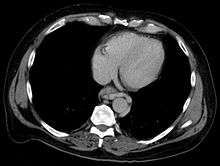

In medicine (gastroenterology), esophageal varices (or oesophageal varices) are extremely dilated sub-mucosal veins in the lower third[1] of the esophagus. They are most often a consequence of portal hypertension, commonly due to cirrhosis; patients with esophageal varices have a strong tendency to develop bleeding.

Esophageal varices are diagnosed with endoscopy.[2]

Dilated submucosal veins are the most prominent histologic feature of esophageal varices. The expansion of the submucosa leads to elevation of the mucosa above the surrounding tissue, which is apparent during endoscopy and is a key diagnostic feature. Evidence of recent variceal hemorrhage includes necrosis and ulceration of the mucosa. Evidence of past variceal hemorrhage includes inflammation and venous thrombosis.